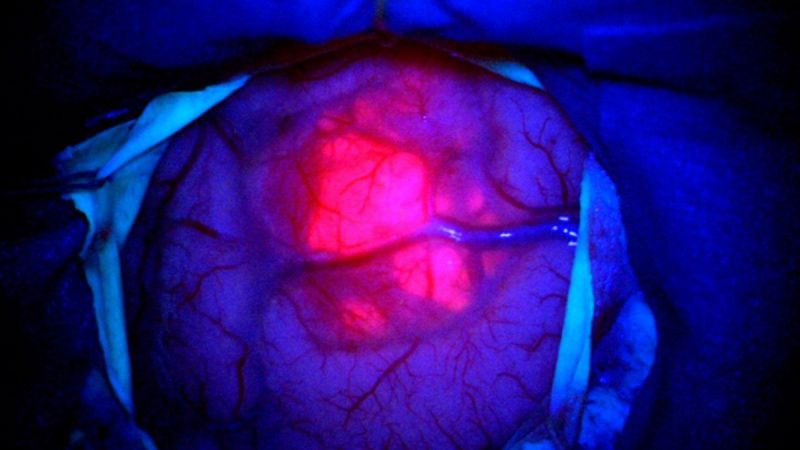

Uma tecnologia que faz células doentes “brilharem” durante a cirurgia já está sendo usada no Hospital da Unimed Litoral, em Balneário Camboriú e promete tornar as neurocirurgias mais precisas e seguras.

O método utiliza um corante especial aliado a luzes específicas, permitindo que os tumores sejam visualizados com mais clareza no microscópio. Na prática, isso ajuda o cirurgião a identificar exatamente onde estão as áreas afetadas, inclusive em regiões profundas ou próximas a partes sensíveis do cérebro.

A técnica é combinada com o monitoramento neurofisiológico, o que contribui para um equilíbrio importante: remover o máximo possível do tumor sem comprometer funções neurológicas.